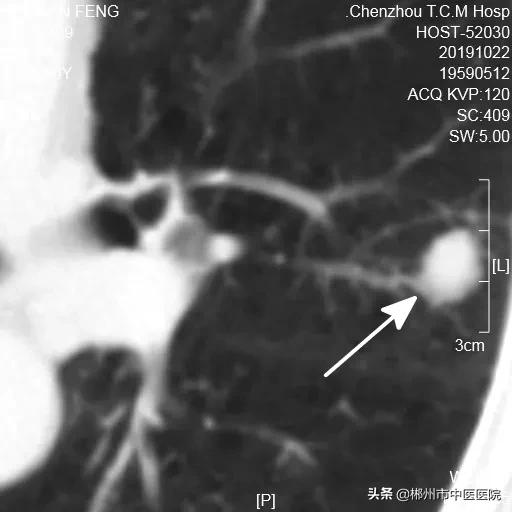

2019年10月住院期间发现左肺占位

陀螺刀治疗前病灶大小15.3X12.4mm